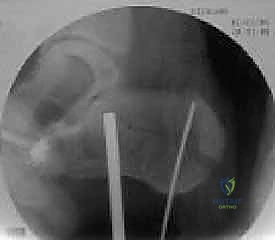

4. التثبيت المؤقت

يتم استخدام أسلاك معدنية دقيقة لتثبيت الشظايا في مكانها مؤقتاً، ثم يتم التحقق من دقة الرد باستخدام جهاز الأشعة السينية داخل غرفة العمليات (C-arm) لضمان عدم وجود أي انزياح ولو بمليمتر واحد.